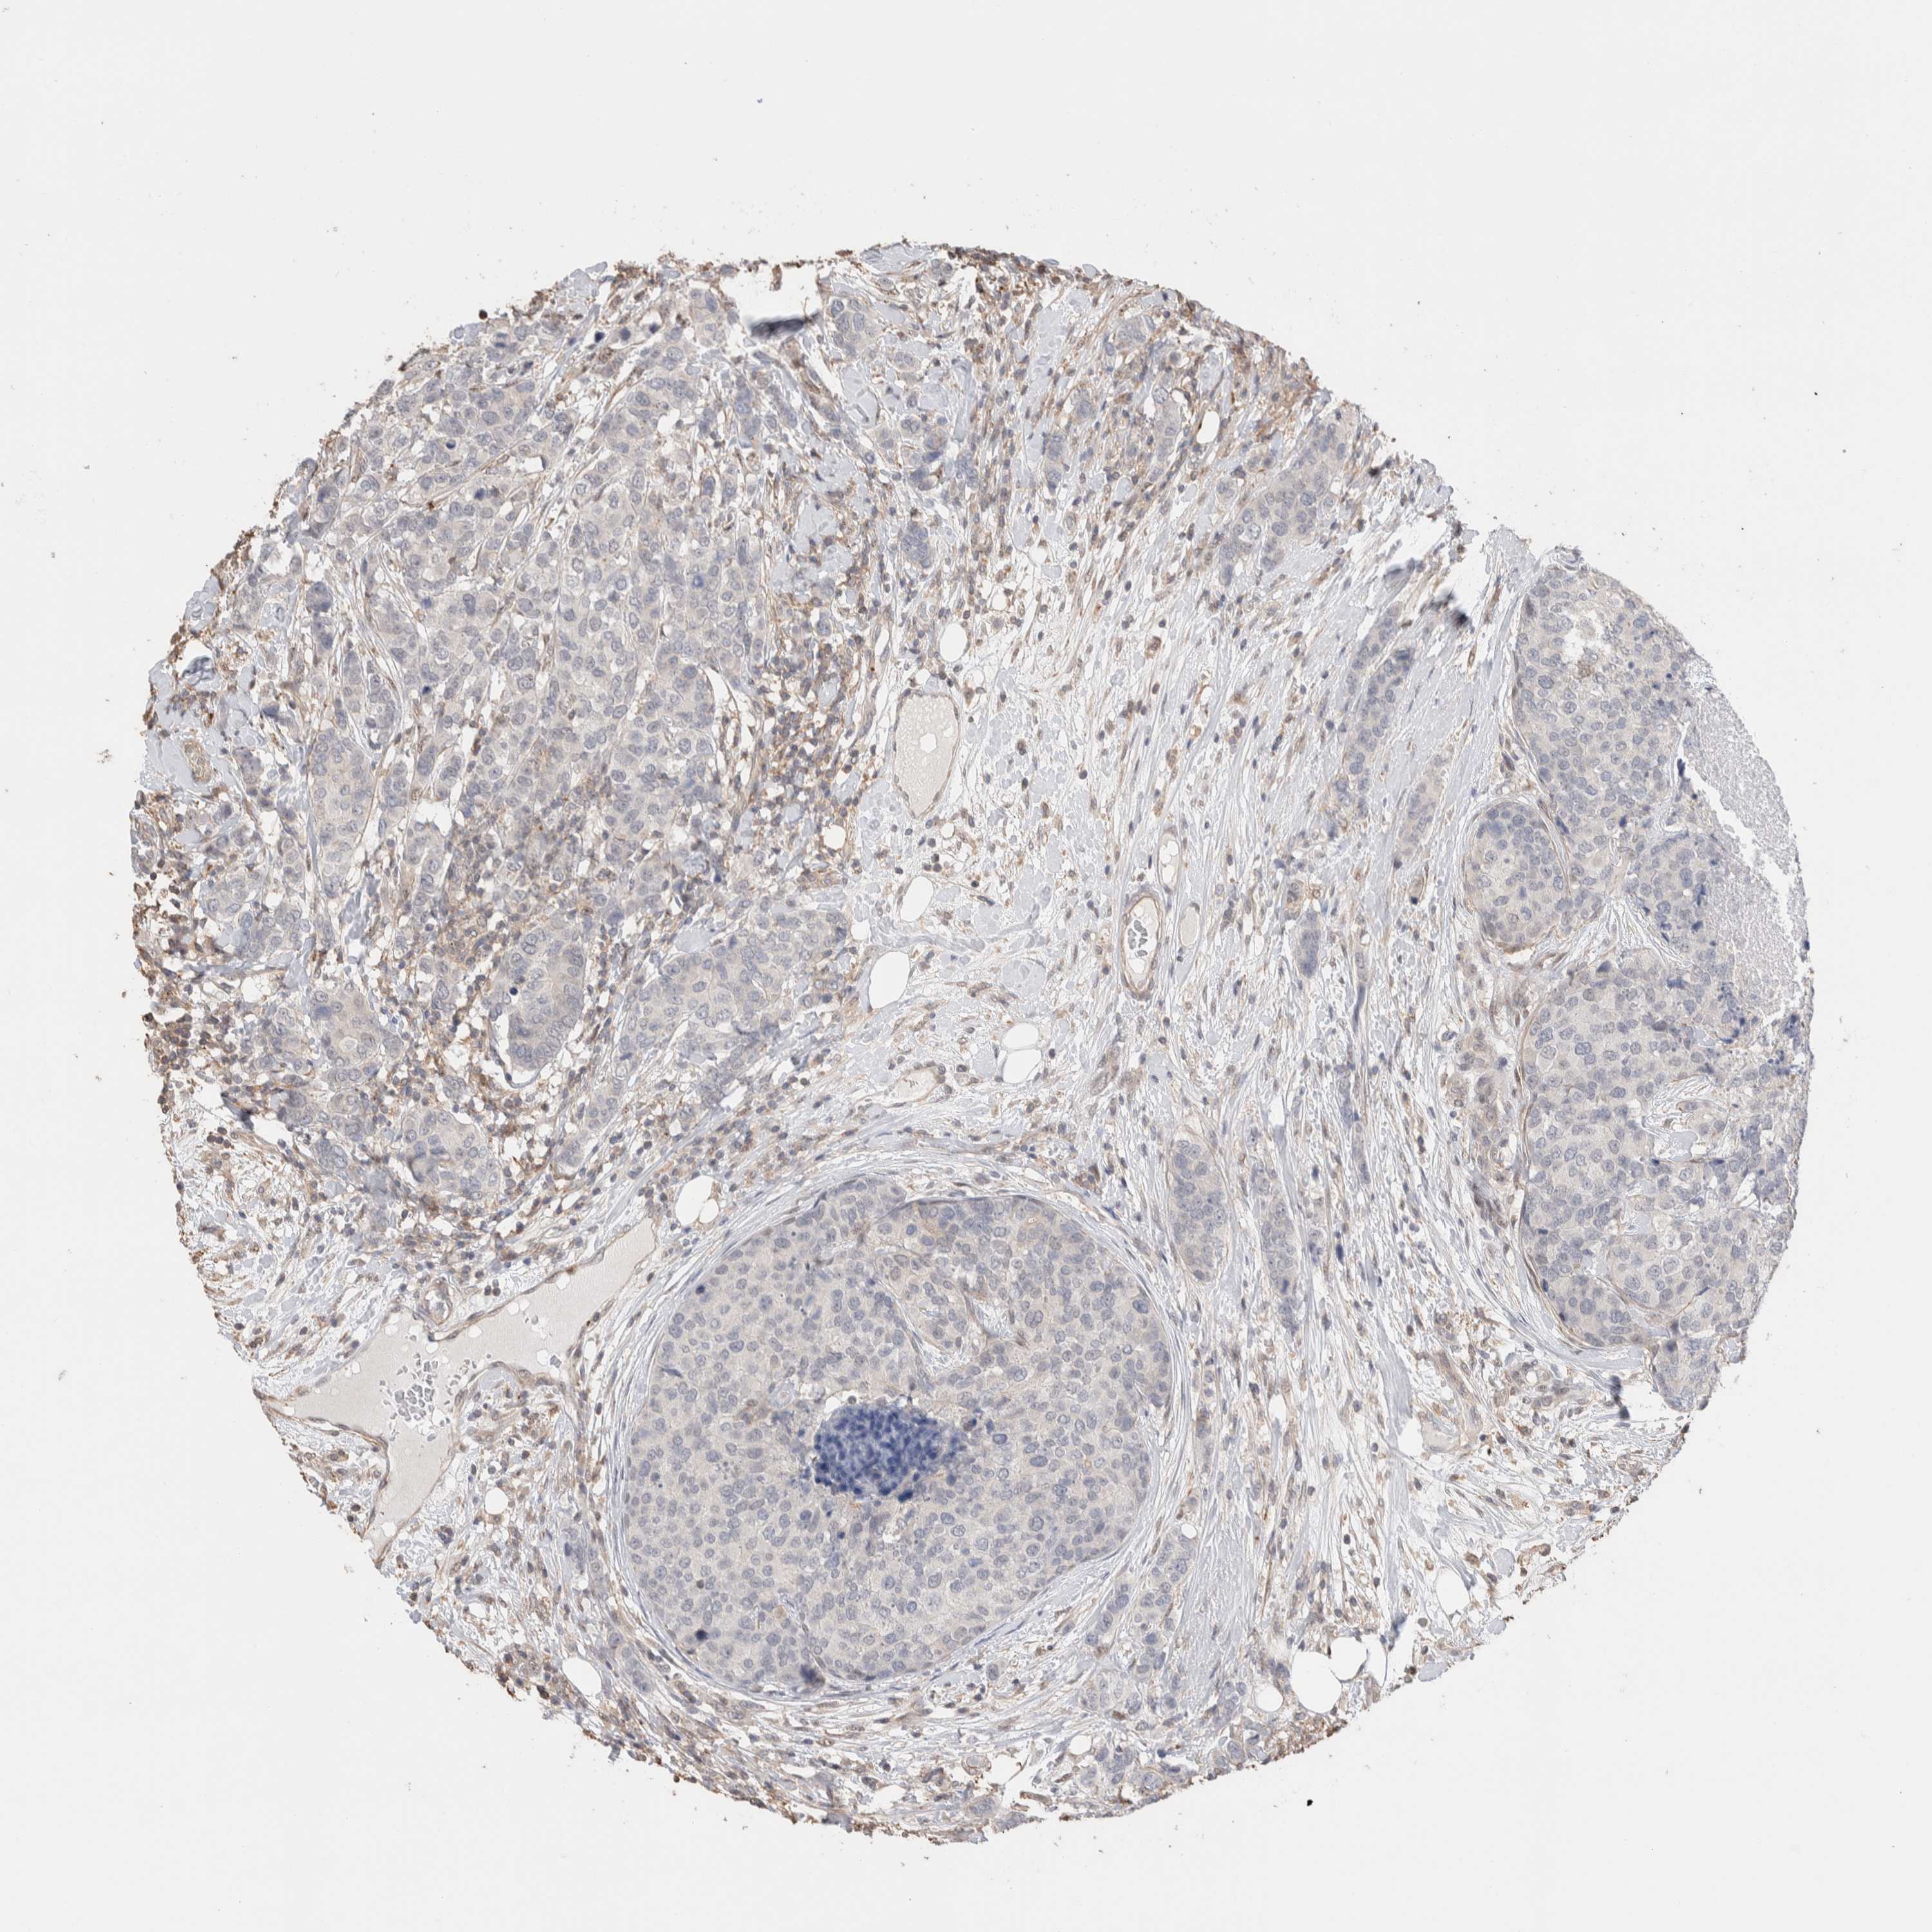

CANCER BREAST CANCER Show tissue menu

BRCA TCGA BRCA VALIDATION PROTEIN EXPRESSION